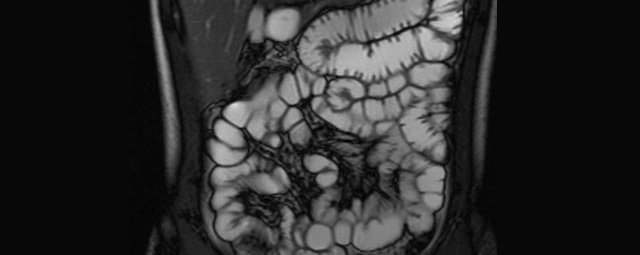

- Dünndarm/Dickdarm

- Chronisch-entzündliche Darmerkrankungen wie Morbus Crohn oder Colitis ulcerosa. Beurteilung der Ausdehnung der Entzündung, Darstellung von Fisteln oder Abszessen bzw. einer Passagebehinderung (MR-Sellink, MR-Kolonographie, beide Untersuchungen nach spezieller Vorbereitung)

- Darstellung bzw. Kontrolle im Verlauf bei perianalen Fisteln und Abszessen

- Verlaufskontrolle des Lokalbefundes nach Rektumentfernung bei Karzinom